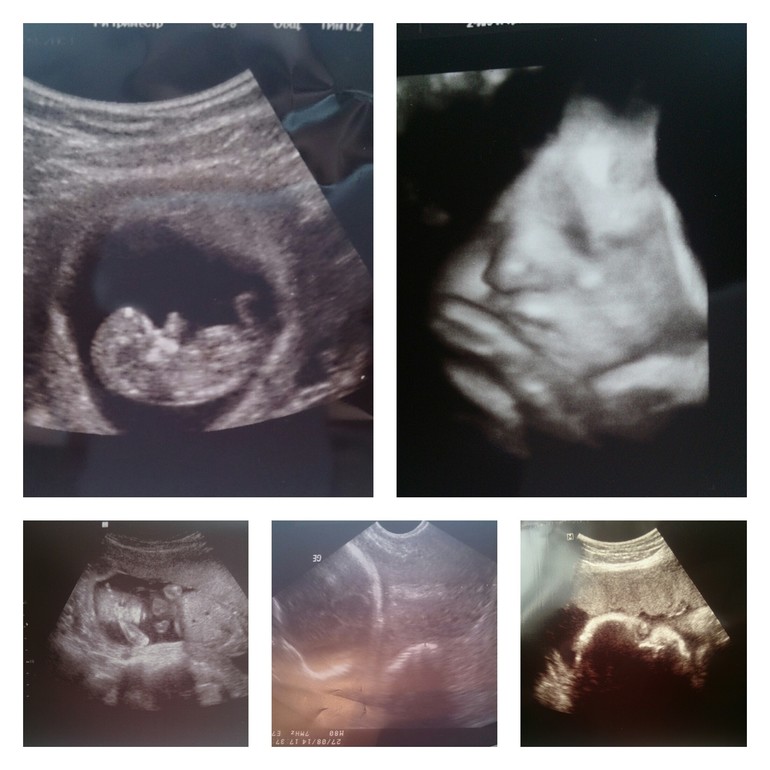

И УЗИфото,с 12 по 36ю

Так и есть))а фоткали всего лишь шейку.Пришла домой,достала фотку и испугалась,черепушка улыбается)

Ржу над черепушкой)))у меня почти такая же фотка ест,Г спрашивает -(тебе полностю сделат ,или что-то отделно)говорю -лицо,а как увидела фото,сразу спрятала его.